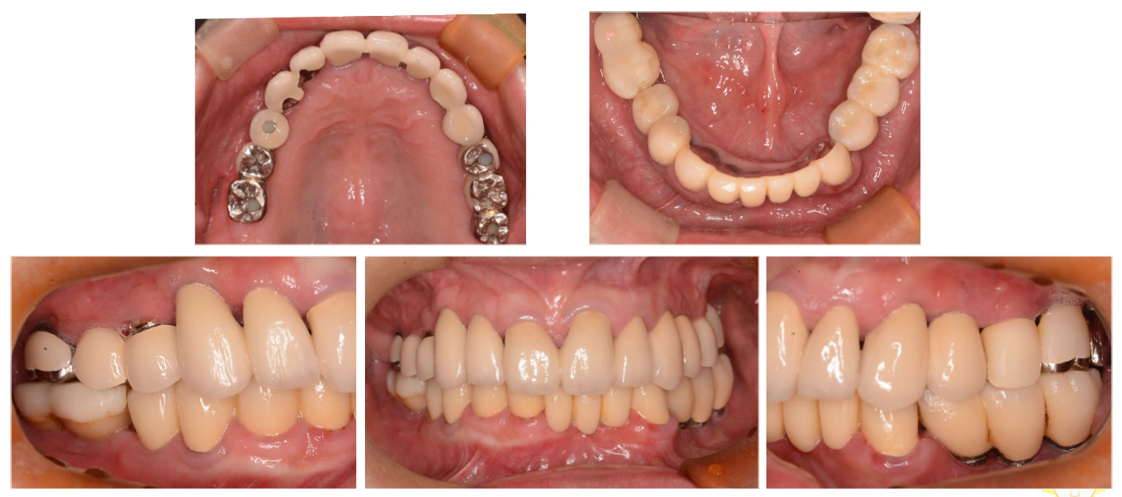

インプラント治療の症例6

(上下の歯が複数本ない・咬合崩壊)

治療前

治療後

| 診断名・主訴 | ①治療の続きをしてほしい ②インプラント希望 |

| 年齢 | 50歳 |

| 治療期間 | 3年間 |

| 治療内容 | インプラント治療 |

| 治療に用いた主な材料、設備機器 | 京セラFINESIAインプラント 上部構造:ジルコニアセラミック |

| 抜歯部位 | 右上8・6・2 左上5・6 |

| 治療費 | 約350万 |

| リスク・副作用 | 術後出血や腫れ |